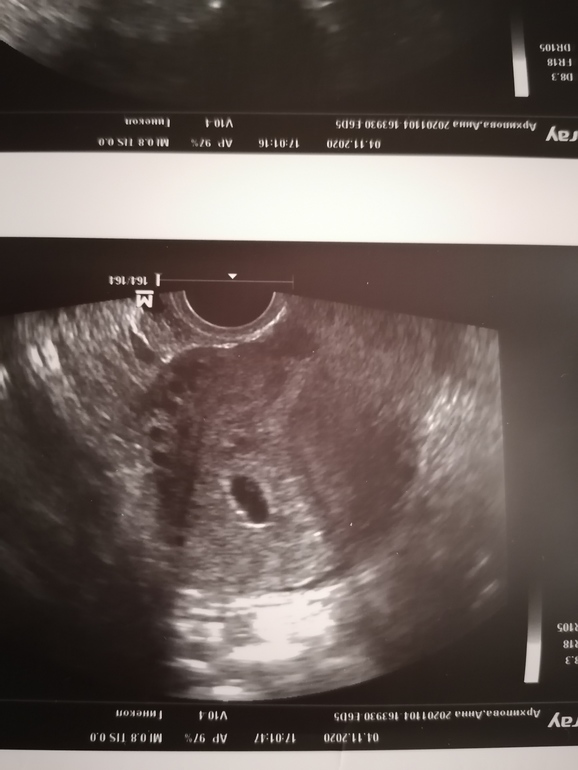

Ну а теперь самые приятные моменты. Я увидела яичко и руки от волнения аж мокрыми стали. Столько эмоций и чувст🥰🥰🥰.

Колобочек растёт тьфу тьфу тьфу хорошо.

ПЯ - 19мм ( но, что-то думаю врач опечаталась, по размерам получается 9мм и это более точный вариант) 🤨

ЖМ - 3мм

Прикрепился в дне матки по передней стенке💙💙💙.

Желтое тело в ЛЯ 18мм с хорошим кровотоком.

Шейка 43мм

Врач сказала все хорошо и на узи через 2 недели, смотреть сердечко и кисту. Вот такие наши новости💙💙💙🥰🥰🥰.

Мой либимый колобочек🙌🙌🙌💙💙💙🥰. Любим тебя и ждём в конце июня🙏🙏🙏.